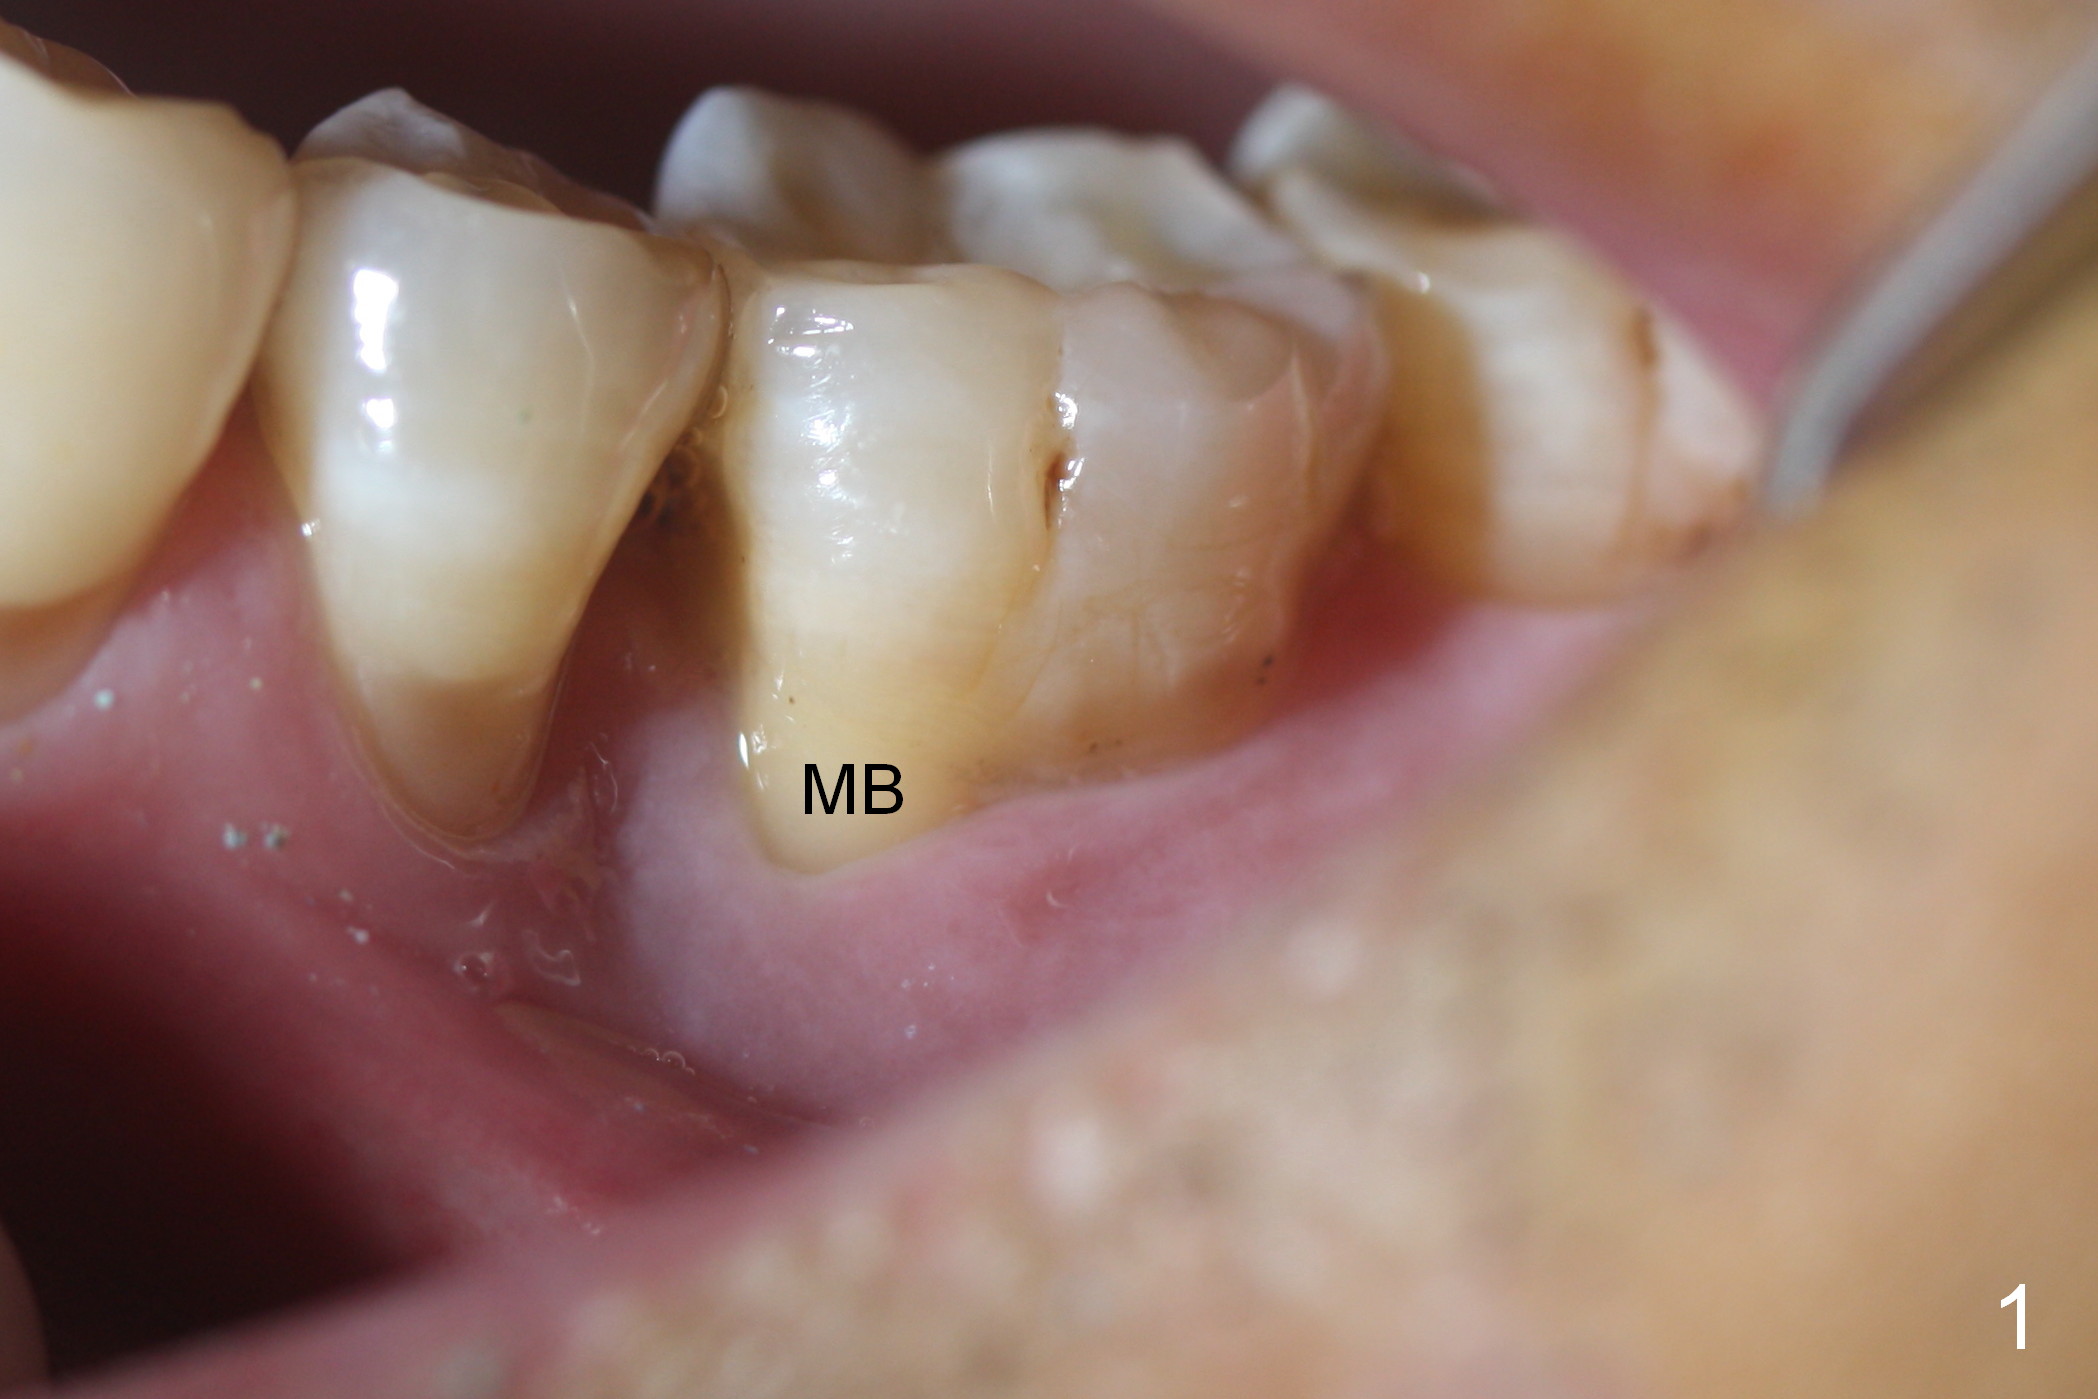

Considering the severe bone loss in the meisal socket, socket preservation is indicated if immediate implant is not feasible. Preop exam shows that the mesiobuccal gingival recession (Fig.1 MB) is not as severe as the mesiolingual one (Fig.2 ML). Because of oozing from the mesial socket, buccal envelop incision is made with flap raising to increase visibility. Probably due to periodontal infection, pain control is difficult. Osteotomy buccal to the Inferior Alveolar Canal proves to be risky. In addition, osteotomy in the mesial socket is more difficult than the distal one (Fig.3). Once the osteotomy depth is determined relative to the superior border of the Inferior Alveolar Canal (4 mm), the osteotomy depth increases by 2 mm. A 5.5x10 mm implant is placed with insertion torque ~ 35 Ncm (Fig.4); a 15 ° angled abutment (5.5 mm in diameter, 4 mm in cuff) is placed mesially. Then the abutment is turned lingually favorable for restoration (Fig.5), the remaining socket is filled with allograft/Osteogen (*) and Collagen Plug.